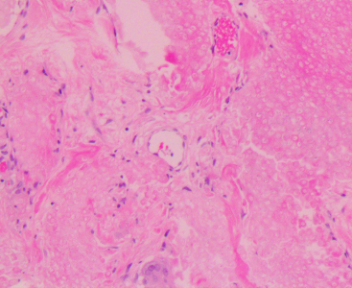

上臂肿物

性别

男

年龄

44岁

临床诊断

肿物性质待查

一般病史

无

标本名称

大体所见

灰白不规则软组织1块1.5x1.5x1cm。